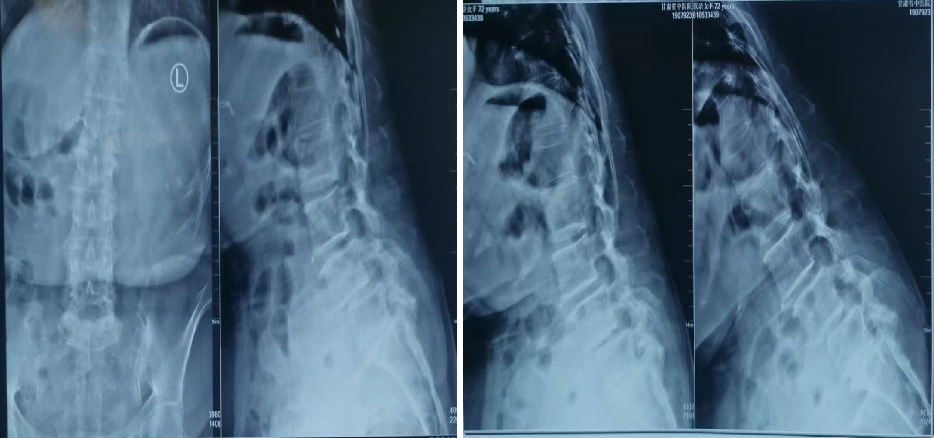

腰椎滑脱该怎么诊治?看这篇就够了!

腰椎滑脱是一种比较常见的疾病,是指其中一节段椎体与下方椎体向前滑动或脱离。